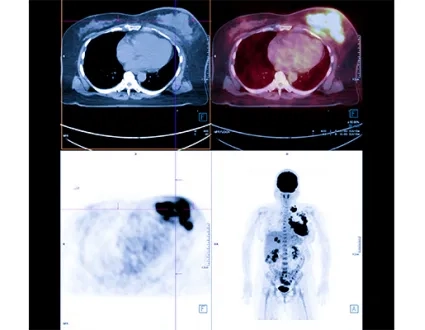

Many different imaging methods can be used in the diagnosis of neuroendocrine tumors, including CT, MR, PET/CT, and ultrasound. PET/CT imaging performed with FDG, a kind of sugar used in the diagnosis of many cancers and in the detection of disease spread, falls short in detecting neuroendocrine cancers. For this reason, special PET/CT scans using smart molecules are used for neuroendocrine cancers. Gallium-68 DOTATATE PET/CT imaging is used to find and image tumor cells in the body at the molecular level. Gallium-68 DOTATATE is accepted as an up-to-date imaging method used for neuroendocrine tumors.